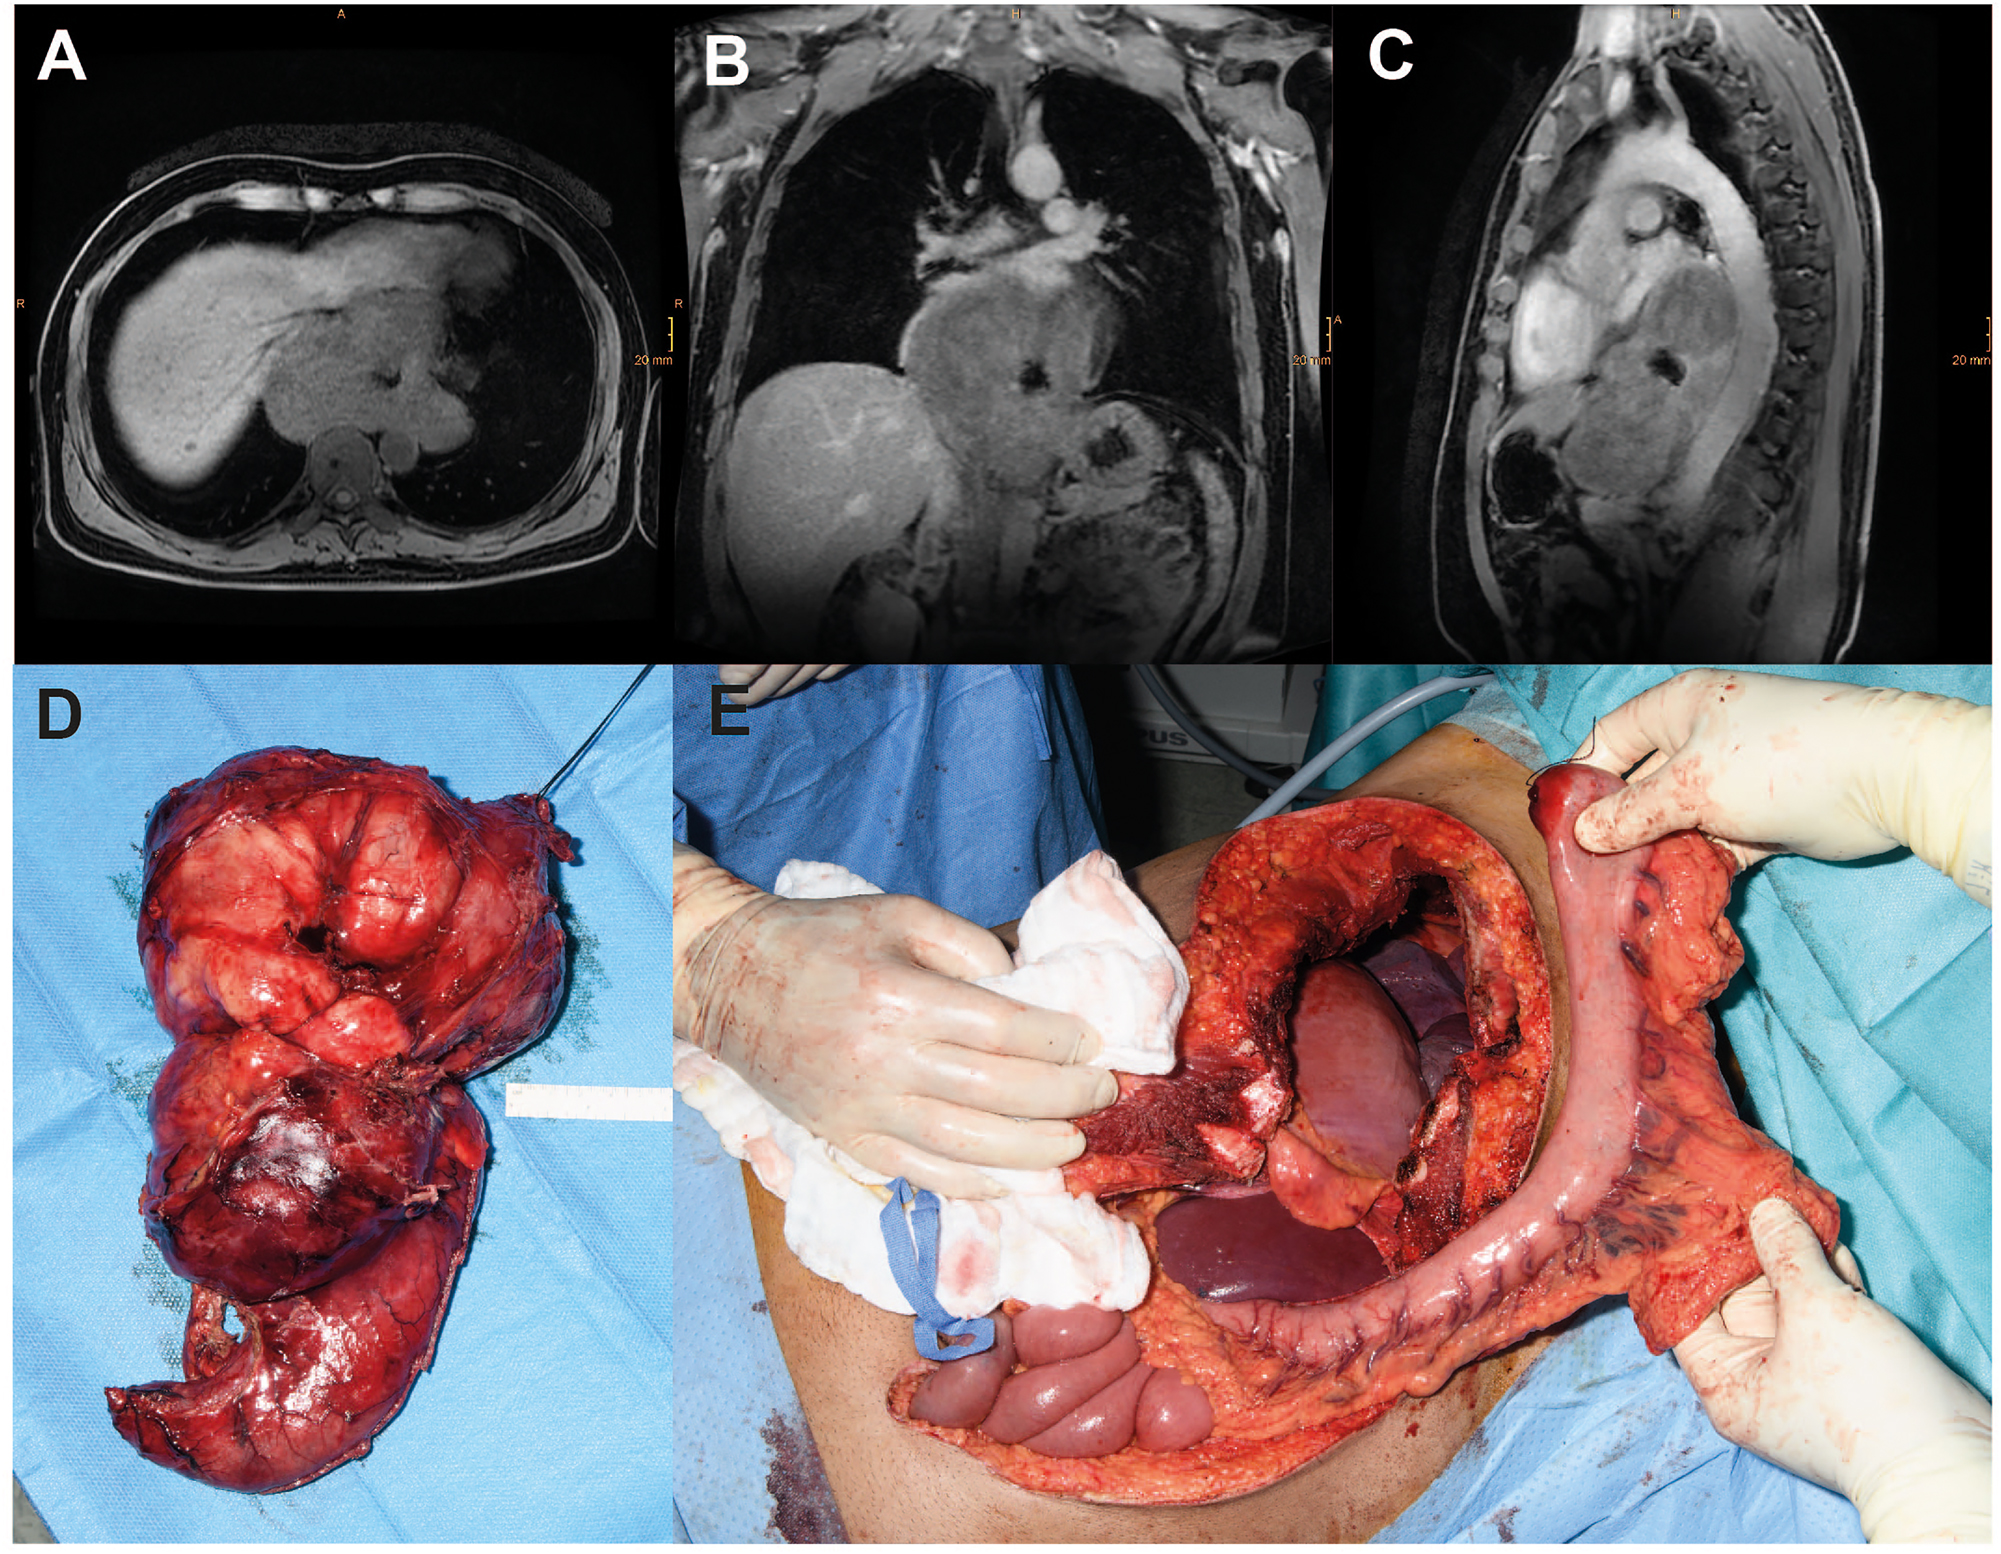

SET above a certain size, specific entities (e.g., malignant GIST with mucosal infiltration), or complications (e.g., central necrosis or abscess formation after biopsy) may not be treatable by enucleation. For oncologic reasons, esophagectomy may also be required for GIST with high-risk stigmata [45]. Figure 3 shows the case of a patient with a large esophageal leiomyoma. Due to the size of the lesion and involvement of the esophagogastric junction with large tumor nodules on both sides of the diaphragm, open surgical thoraco-laparotomy was required for en bloc tumor removal, and continuity was reconstructed with a gastric pull-up procedure and anastomosis at the level of the azygos vein according to Ivor Lewis.

Case of a male patient with a giant (17 × 14 × 8 cm) esophageal leiomyoma with abscess following diagnostic biopsy. Transverse (A), coronal (B) and sagittal (C) magnetic resonance imaging planes of the tumor. (D) Intraoperative images of the resected specimen and (E) the situs after thoraco-laparotomy before reconstruction with interposition of the tubulized stomach.